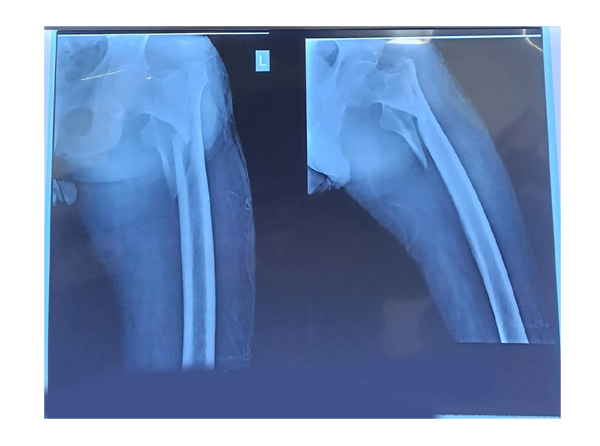

Joint Replacement Surgery

Joint replacement surgery is a transformative procedure designed to re